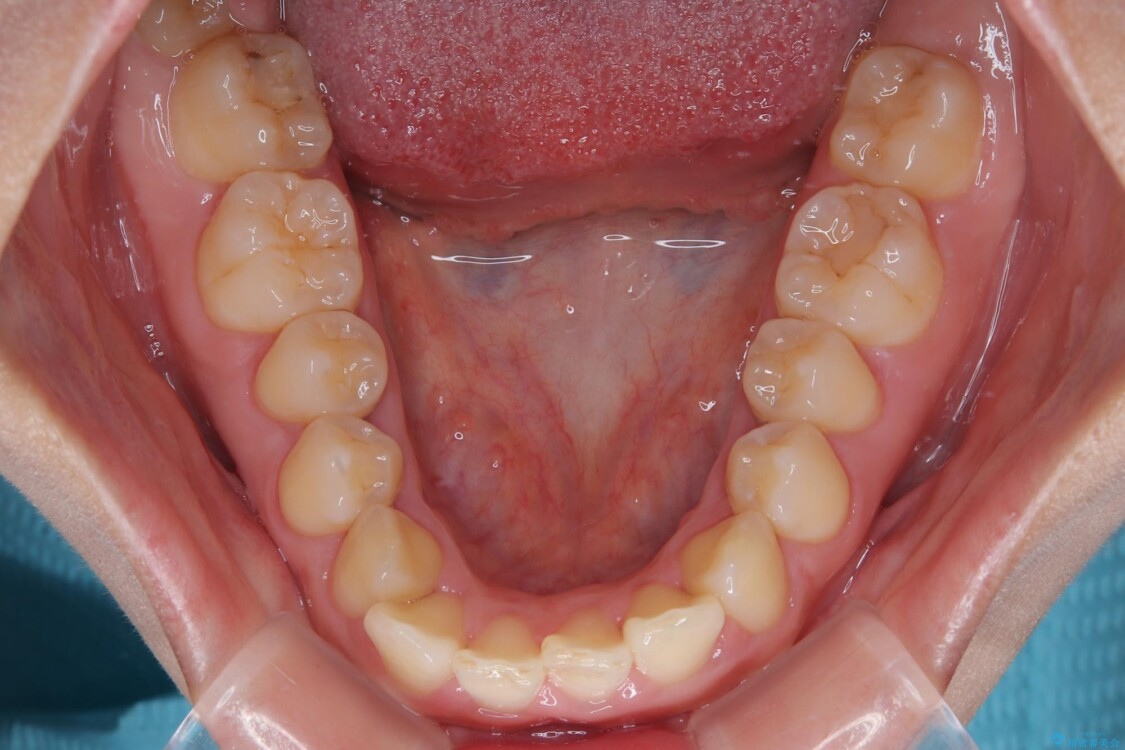

治療前

• 目立ちにくい表側装置で1年完了!狭いアーチを側方拡大し前歯のデコボコを整えた症例 治療前画像